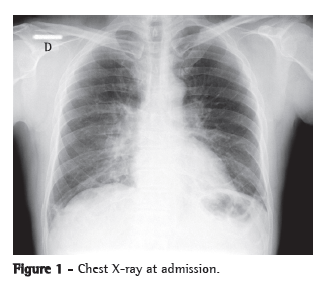

A chest X-ray showed worsening of the bilateral alveolar infiltrate, and a chest CT scan showed multifocal ground-glass infiltrate (Figures 1 and 2).

The most common radiological manifestations of influenza pneumonia consist of reticulonodular opacities, with or without superimposed areas of consolidation. Less commonly, patients with influenza pneumonia can present with focal areas of consolidation, typically in the lower lobes, without apparent reticular or reticulonodular opacities. The radiological abnormalities typically resolve in approximately three weeks. Consolidations can occur due to secondary bacterial pneumonia.(7,8)